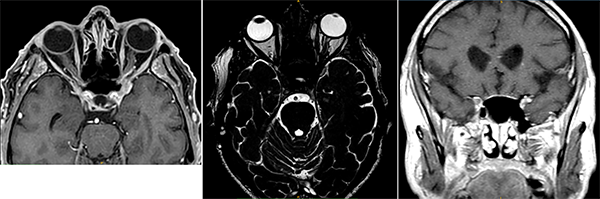

Se indicó RM de encéfalo y órbitas, con contraste, que evidenció un sutil realce asimétrico en el seno cavernoso anterior, fisura orbitaria superior y ápice orbitario (fig. 2).

Figura 2. RM de encéfalo y órbitas.